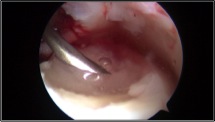

Nei casi più importanti, dove le lesioni cartilaginee sono più gravi e localizzate in zone di carico dell’astragalo, una valida soluzione è rappresentata dall’utilizzo di tecniche chirurgiche avanzate di riparazione cartilaginea che utilizzano supporti tridimensionali in grado di veicolare le cellule cartilaginee e colmare così il difetto che si è creato. Queste tecniche possono essere eseguite anche in artroscopia con maggior rispetto dell’articolazione e tempi di recupero post-operatorio di circa 3-4 mesi.